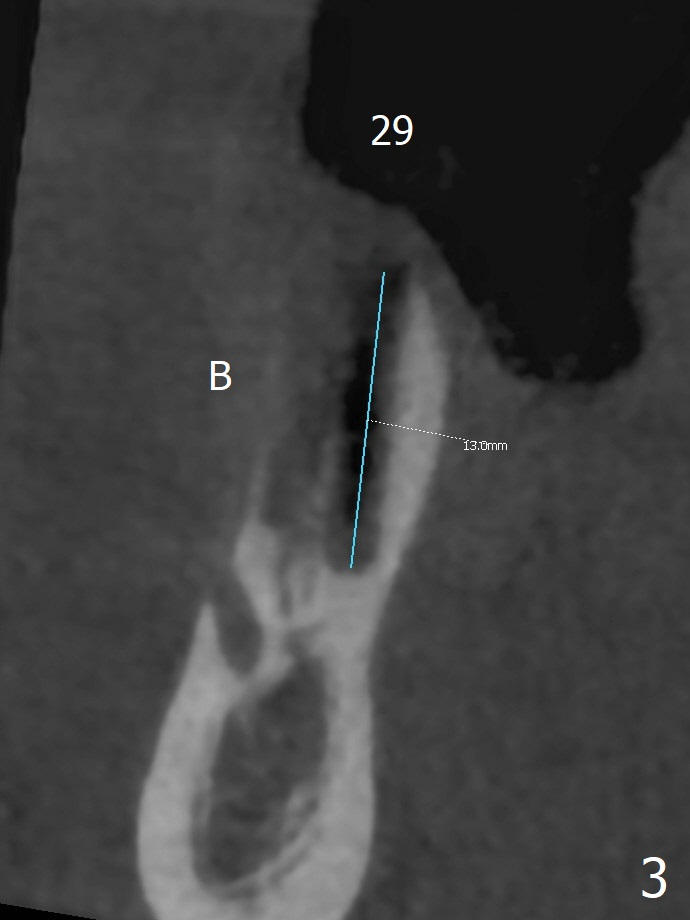

The buccal gingiva is recessive at #29 and 30 (Fig.1). Incision reveals buccal implant thread exposure with circum-ferential granulation tissue (Fig.2 *). Immediate post implant removal at #29, osteotomy is initiated lingual (Fig.3 (intraop CT, coronal section) ). A smaller and shorter implant (3x12 mm vs. 3.5x13 mm) is placed away from buccal (Fig.4 B, 5).